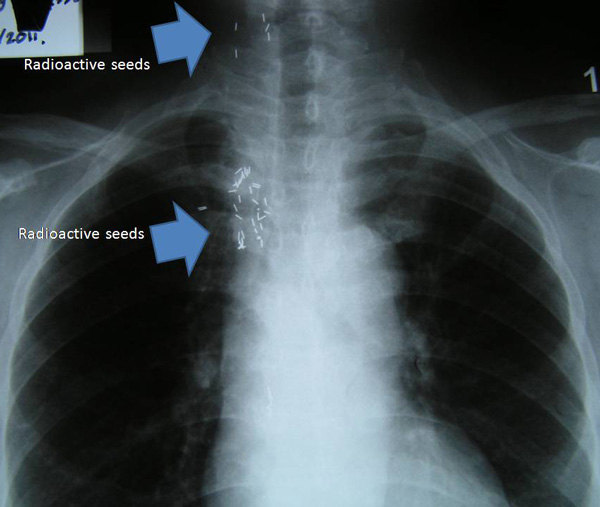

Riwayat medis

Pasien ini terdiagnosa kanker payudara yang telah menyebar ke tulang-tulangnya. Dia pergi ke Cina untuk berobat – menggunakan kemoterapi, cryoablation dan radioactive particle seed implant. Pada tahun 2008, dia pergi ke Cina sebanyak tiga kali, dua kali di tahun 2009 dan satu kali di tahun 2010. Pengobatan ini tidak lantas membuatnya sembuh. Sejak bulan Februari 2011, dia tidak bisa berjalan. Kaki sebelah kirinya sakit dan bengkak. Dua bulan kemudian dia menjalani operasi untuk kaki sebelah kirinya. Namun sakitnya tidak hilang.

Dokter di Kuching menyarankan untuk menjalani kemoterapi. Tetapi dia menolak. Keluarga memutuskan untuk membawanya ke China untuk perawatan medis. Dia menerima perawatan seperti kemoterapi, cryoablasi dan particle seed radioaktif di rumah sakit China.